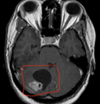

C = nucleo caudado P = Putamen S = nucleo estriado ## Footnote En la foto de abajo hay perdida del nucleo caudado. Comparar con la foto de arriba Ventriculos dilatados por perdida de masa encefalica = hidrocefalia ex vacuo